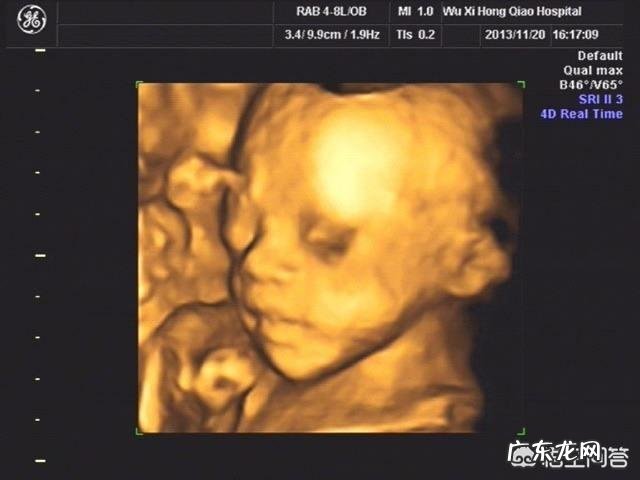

四维彩超主要是检查胎儿有无肢体五官畸形的检查 , 一般是孕24周左右做比较好的 , 这个时候可以清楚的显示

文章插图

因为四维是要检查全身的结构异常 , 需要胎儿配合 , 才能看的全面 。胎儿需要变换不同的体位 , 才有利于医生检查 。20-28周 , 胎儿个头还不是很大 , 子宫的空间又很大 , 胎儿可以自由的活动 , 对检查是有帮助的 。

20-28周 , 骨骼的回声还不是很强 , 对检查结果影响很小 , 有利于看到胎儿真实的情况 。

胎儿的头面部:眼睛、鼻子、嘴巴的结构是否异常 。

胎儿的器官:心脏、脾脏、肾脏、肠道等结构是否完整 。

胎儿的四肢:双足、双脚结构是否异常 。

能检查胎儿脑积水、唇裂、脊柱裂等结构问题 。对智力、视力、听力、代谢疾病、先天心脏病等疾病是不能检查出来的 。